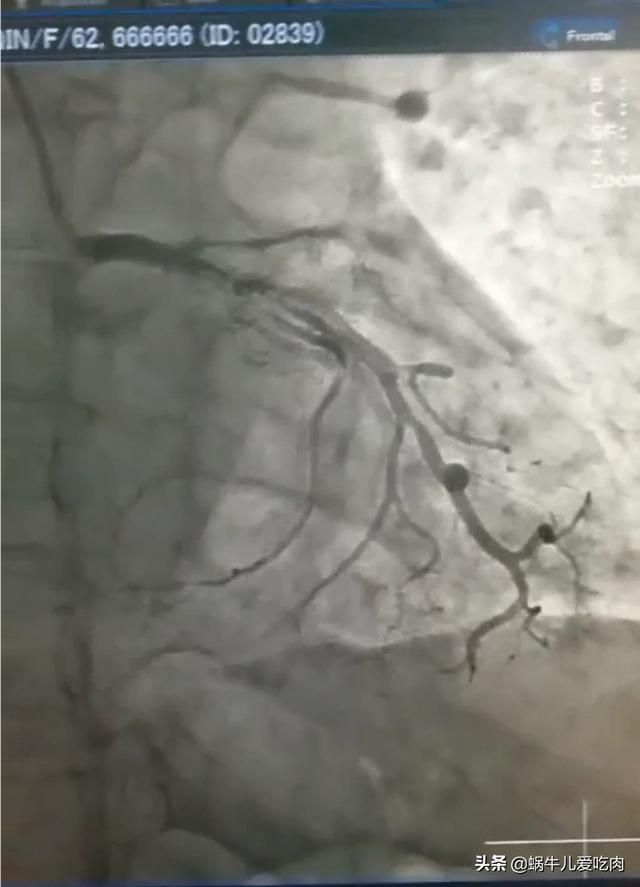

Mais ensuite.Depuis l'échographie, la tomodensitométrie coronaire et surtout la coronarographie, le diagnostic de la maladie coronarienne n'est plus un problème.Il s'agit notamment de pouvoir voir exactement quel vaisseau sanguin du cœur est bloqué et dans quelle mesure chez ce patient.

En général, lorsque nos médecins soupçonnent que vous souffrez d'une maladie coronarienne, ils vous demandent de passer une échographie ou un scanner coronarien pour vérifier si votre cœur est hypertrophié, si vous souffrez d'une cardiomyopathie, d'une maladie valvulaire, etc.Bien sûr, ce scanner coronarien ne peut effectuer qu'un dépistage de la maladie coronarienne, en général, comme le scanner coronarien, s'il n'y a pas de problème, ce n'est pas un gros problème.Mais siNous avons constaté qu'il y avait un problème, mais pour l'instant nous ne pouvons pas dire directement que ce patient doit souffrir d'une maladie coronarienne et qu'il doit subir une angiographie coronarienne.。

Il s'agit d'introduire un tube dans le cœur et d'effectuer une imagerie sélective qui permet de voir les vaisseaux sanguins à l'endroit voulu et de déterminer la quantité de vaisseaux sanguins obstrués.

Il est donc important de rappeler que la coronarographie est l'examen de référence pour le diagnostic de la maladie coronarienne, tandis que la tomodensitométrie coronarienne ne peut être qu'un test de dépistage.

4. L'imagerie des artères coronaires par tomodensitométrie spiralée multicouche (CTA), que nous appelons souvent la CTA cardiaque, peut être utilisée pour déterminer le degré de sténose de la lumière coronaire et de calcification de la paroi, pour déterminer la distribution de la plaque à l'intérieur de la paroi de l'étendue de la plaque et la nature d'une certaine importance, la CTA des artères coronaires a une valeur prédictive négative élevée, s'il n'y a pas de lésions sténosées, ne peut généralement pas être un examen invasif, mais le degré de sténose de son jugement a encore une certaine limite, en particulier en cas de calcification de la paroi. Toutefois, sa capacité à déterminer le degré de sténose reste limitée, en particulier en présence de calcifications.

2, CTA coronaire : il est considéré comme l'un des deux tests les plus importants pour les patients souffrant de maladie coronarienne, il permet de voir visuellement les vaisseaux sanguins avec ou sans blocage de sténose, mais comme il s'agit d'une image statique, il y a un certain degré de variabilité, et ne peut que déterminer la présence ou l'absence de blocage de sténose, pour fournir un support pour l'imagerie ultérieure ou non.

La tomodensitométrie coronaire est un test non invasif qui permet de détecter la présence et l'étendue d'une sténose de l'artère coronaire, tandis que l'angiographie coronaire est l'examen de référence pour le diagnostic de la maladie coronaire, qui permet de détecter l'emplacement et l'étendue de la sténose et de procéder à une intervention.